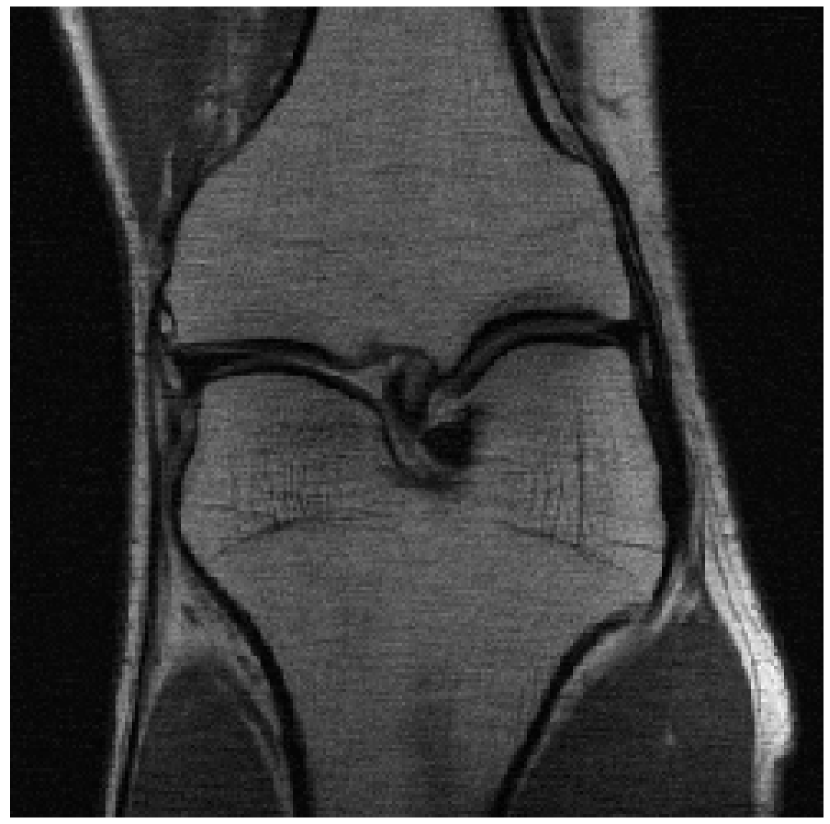

We evaluated our models on three data sets: the validation set as in Zbontar et al. (2018), and the test and challenge sets through the fastMRI website. A summary of these evaluations can be found in table 1111Results on the challenge data set will be added once publicly available.. To assess image quality more closely, we show some exemplary reconstructions from each model in figure 1.

(b) Multi-Coil 4-Fold

Reconstruction

Refer to caption

Figure 1: Example reconstructions. The reconstructions visually improve the ground truth images, suggesting a strong prior.